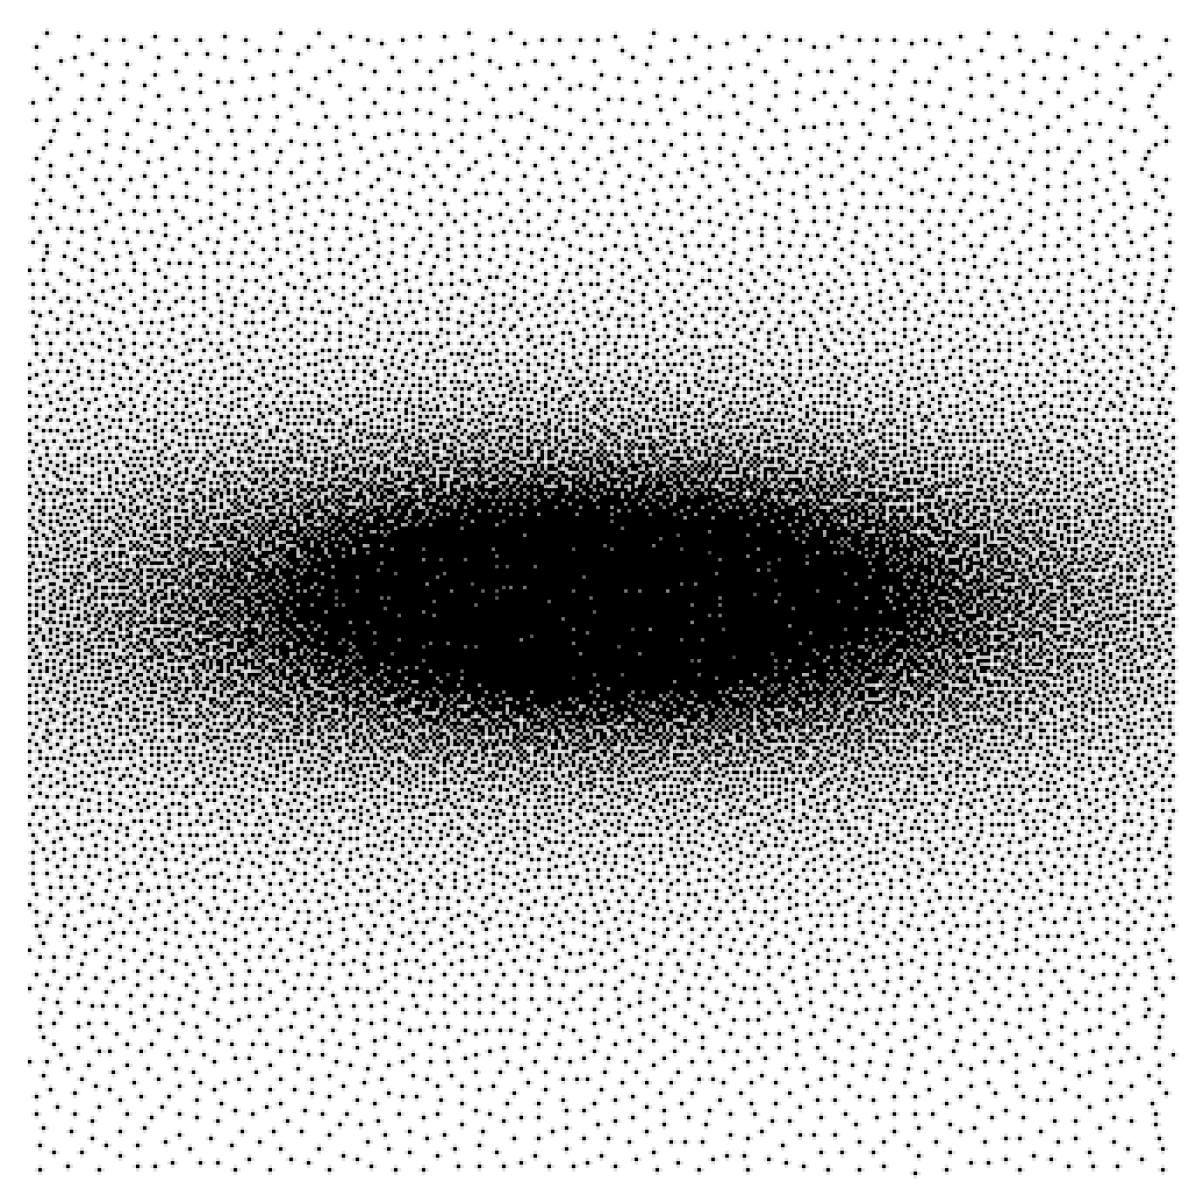

Training mismatch issue

While model-based reconstruction networks provide state-of-the art results in a large panel of applications, it is now well established that they suffer from a lack of adaptivity. This means that a network trained for a specific operator may have a significant performance drop if used for another operator . This drop can be evaluated as follows. Let denote two different operator parametrizations. Let and . Assume that and are the weights of a reconstruction network optimized for and respectively. We compare the quality of and in the third and fourth rows of Fig. 1. Observe the significant performance difference.

| Test case | MRI | CT | Deblurring |

To avoid this pitfall, we propose to train the network by minimizing (4) instead of (3). After providing some theoretical hints on why a favorable behavior may occur, we will carefully evaluate the performance of the resulting networks in Section 6 for MR image reconstruction from under-sampled data, CT imaging and image deblurring. We conclude that this learning approach yields a reconstruction network which is significantly more stable to variations of the forward operator. In addition, the performance of an unrolled network trained on a restricted family is only marginally worse than that of a network that would be trained and used for a single operator. It therefore provides a satisfactory answer to the adaptivity issue. We also address several questions raised by our methodology. Can the unrolled network trained on a family extrapolate to unseen operators? How to sample the space of admissible operators? What is the gain of this approach in comparison to more “universal approaches” such as plug-and-play (P&P) priors?

Model mismatch issue

Assume that we observe . Unfortunately, we only have access to an approximate knowledge of the true forward model . This can be due to an imprecise calibration of the sensing device or to the motion of a patient in a scanner for instance. We then face a blind inverse problem. A problem solved with such a model mismatch (i.e. with the operator in place of ), can lead to catastrophic reconstruction results, as illustrated in the last row of Fig. 1.

The drop of peak signal-to-noise ratio (PSNR) when using a network trained with the wrong operator can be as high as dB for the denoising net on the MRI experiment (see trained on , applied on ). This drop is more moderate, but yet really significant (MRI: dB, CT: dB, Blur: dB) for the unrolled net. This is a striking illustration of the strong dependency of a reconstruction network to the operator used at the training stage. We illustrate the artifacts that can appear when the operator is trained on a different operator for the MRI application in Fig. 4. We can clearly see horizontal stripes oscillating at a high frequency, suggesting that the network did not properly learn to reconstruct the corresponding Fourier coefficients.